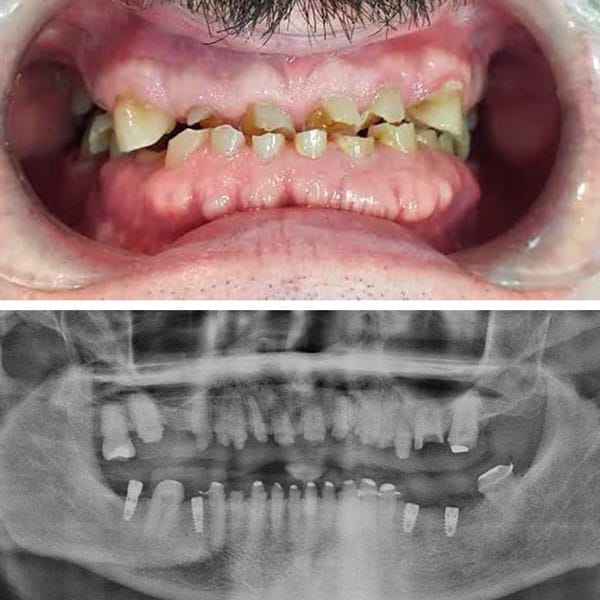

CASOS CLÍNICOS